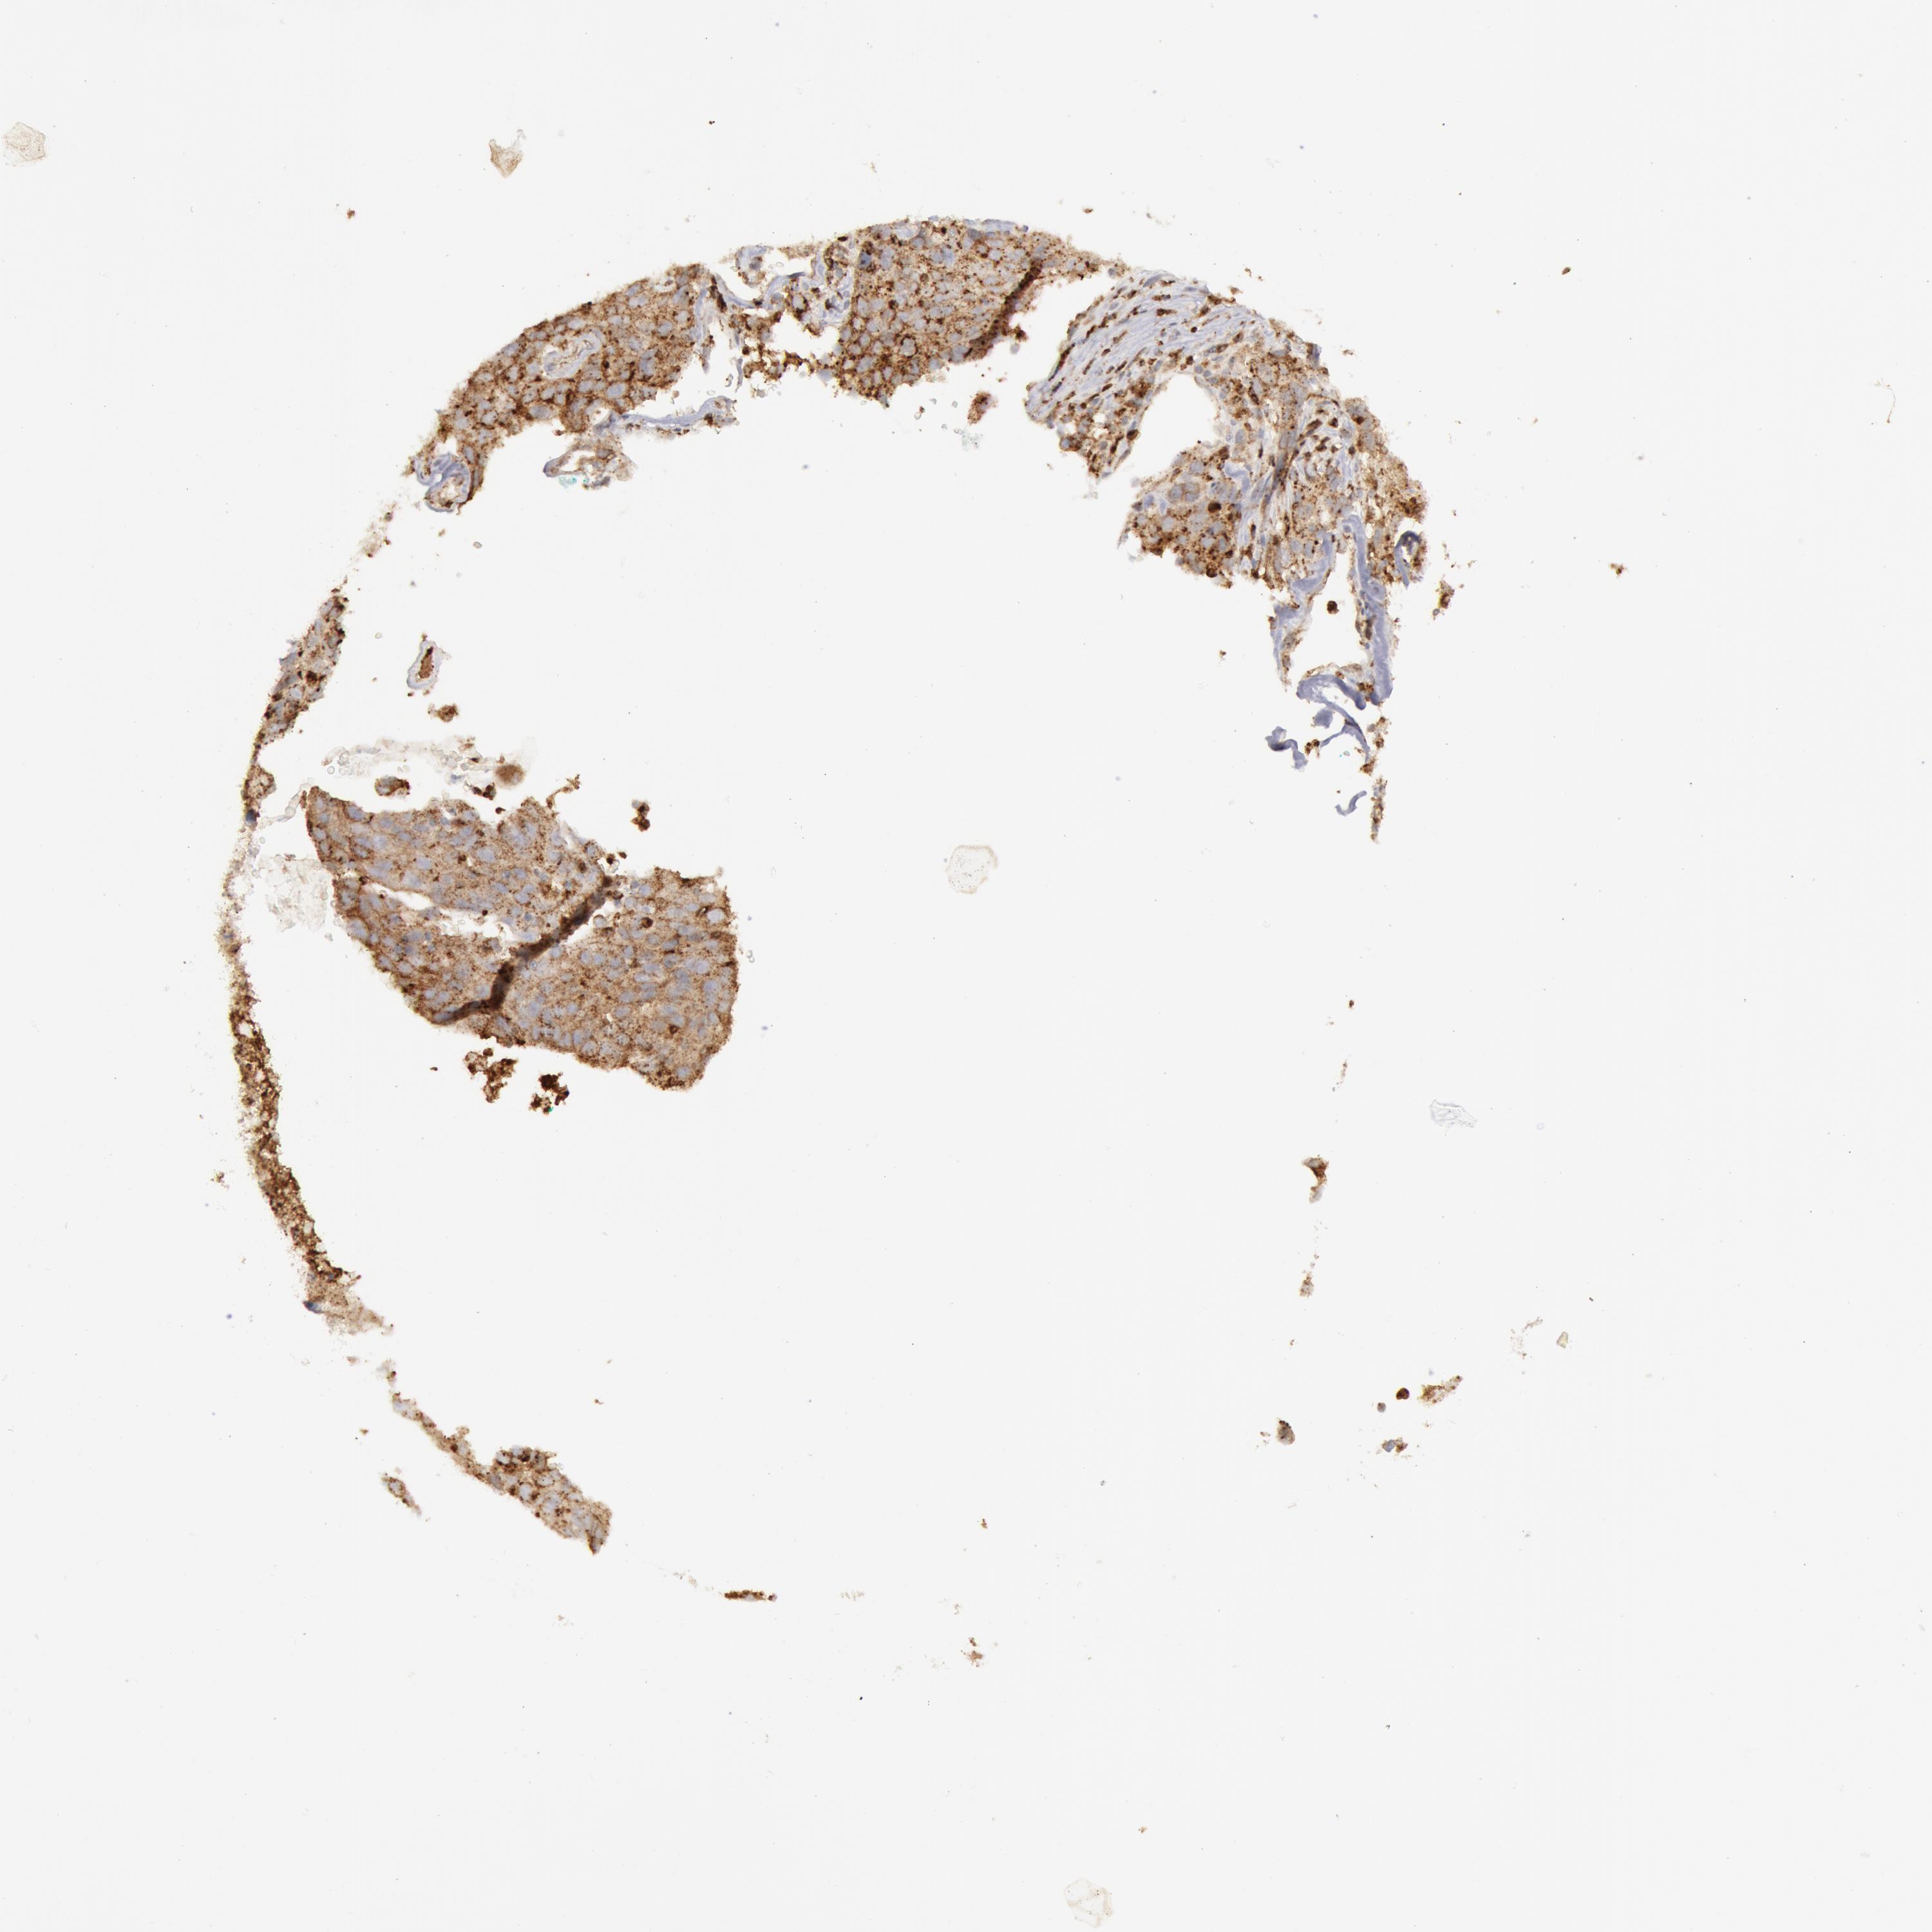

CANCER LUNG CANCER Show tissue menu

BREAST CANCER CARCINOID CERVICAL CANCER COLORECTAL CANCER ENDOMETRIAL CANCER GLIOMA HEAD AND NECK CANCER LIVER CANCER LUNG CANCER LYMPHOMA

MELANOMA OVARIAN CANCER PANCREATIC CANCER PROSTATE CANCER RENAL CANCER SKIN CANCER STOMACH CANCER TESTIS CANCER THYROID CANCER UROTHELIAL CANCER

LUAD TCGA LUAD VALIDATION LUSC TCGA LUSC VALIDATION PROTEIN LUAD CPTAC PROTEIN LUSC CPTAC PROTEIN EXPRESSION

ANTIBODIES

AND

VALIDATION

Lung cancer

Human cancer

Lung adenocarcinoma

Lung squamous cell carcinoma